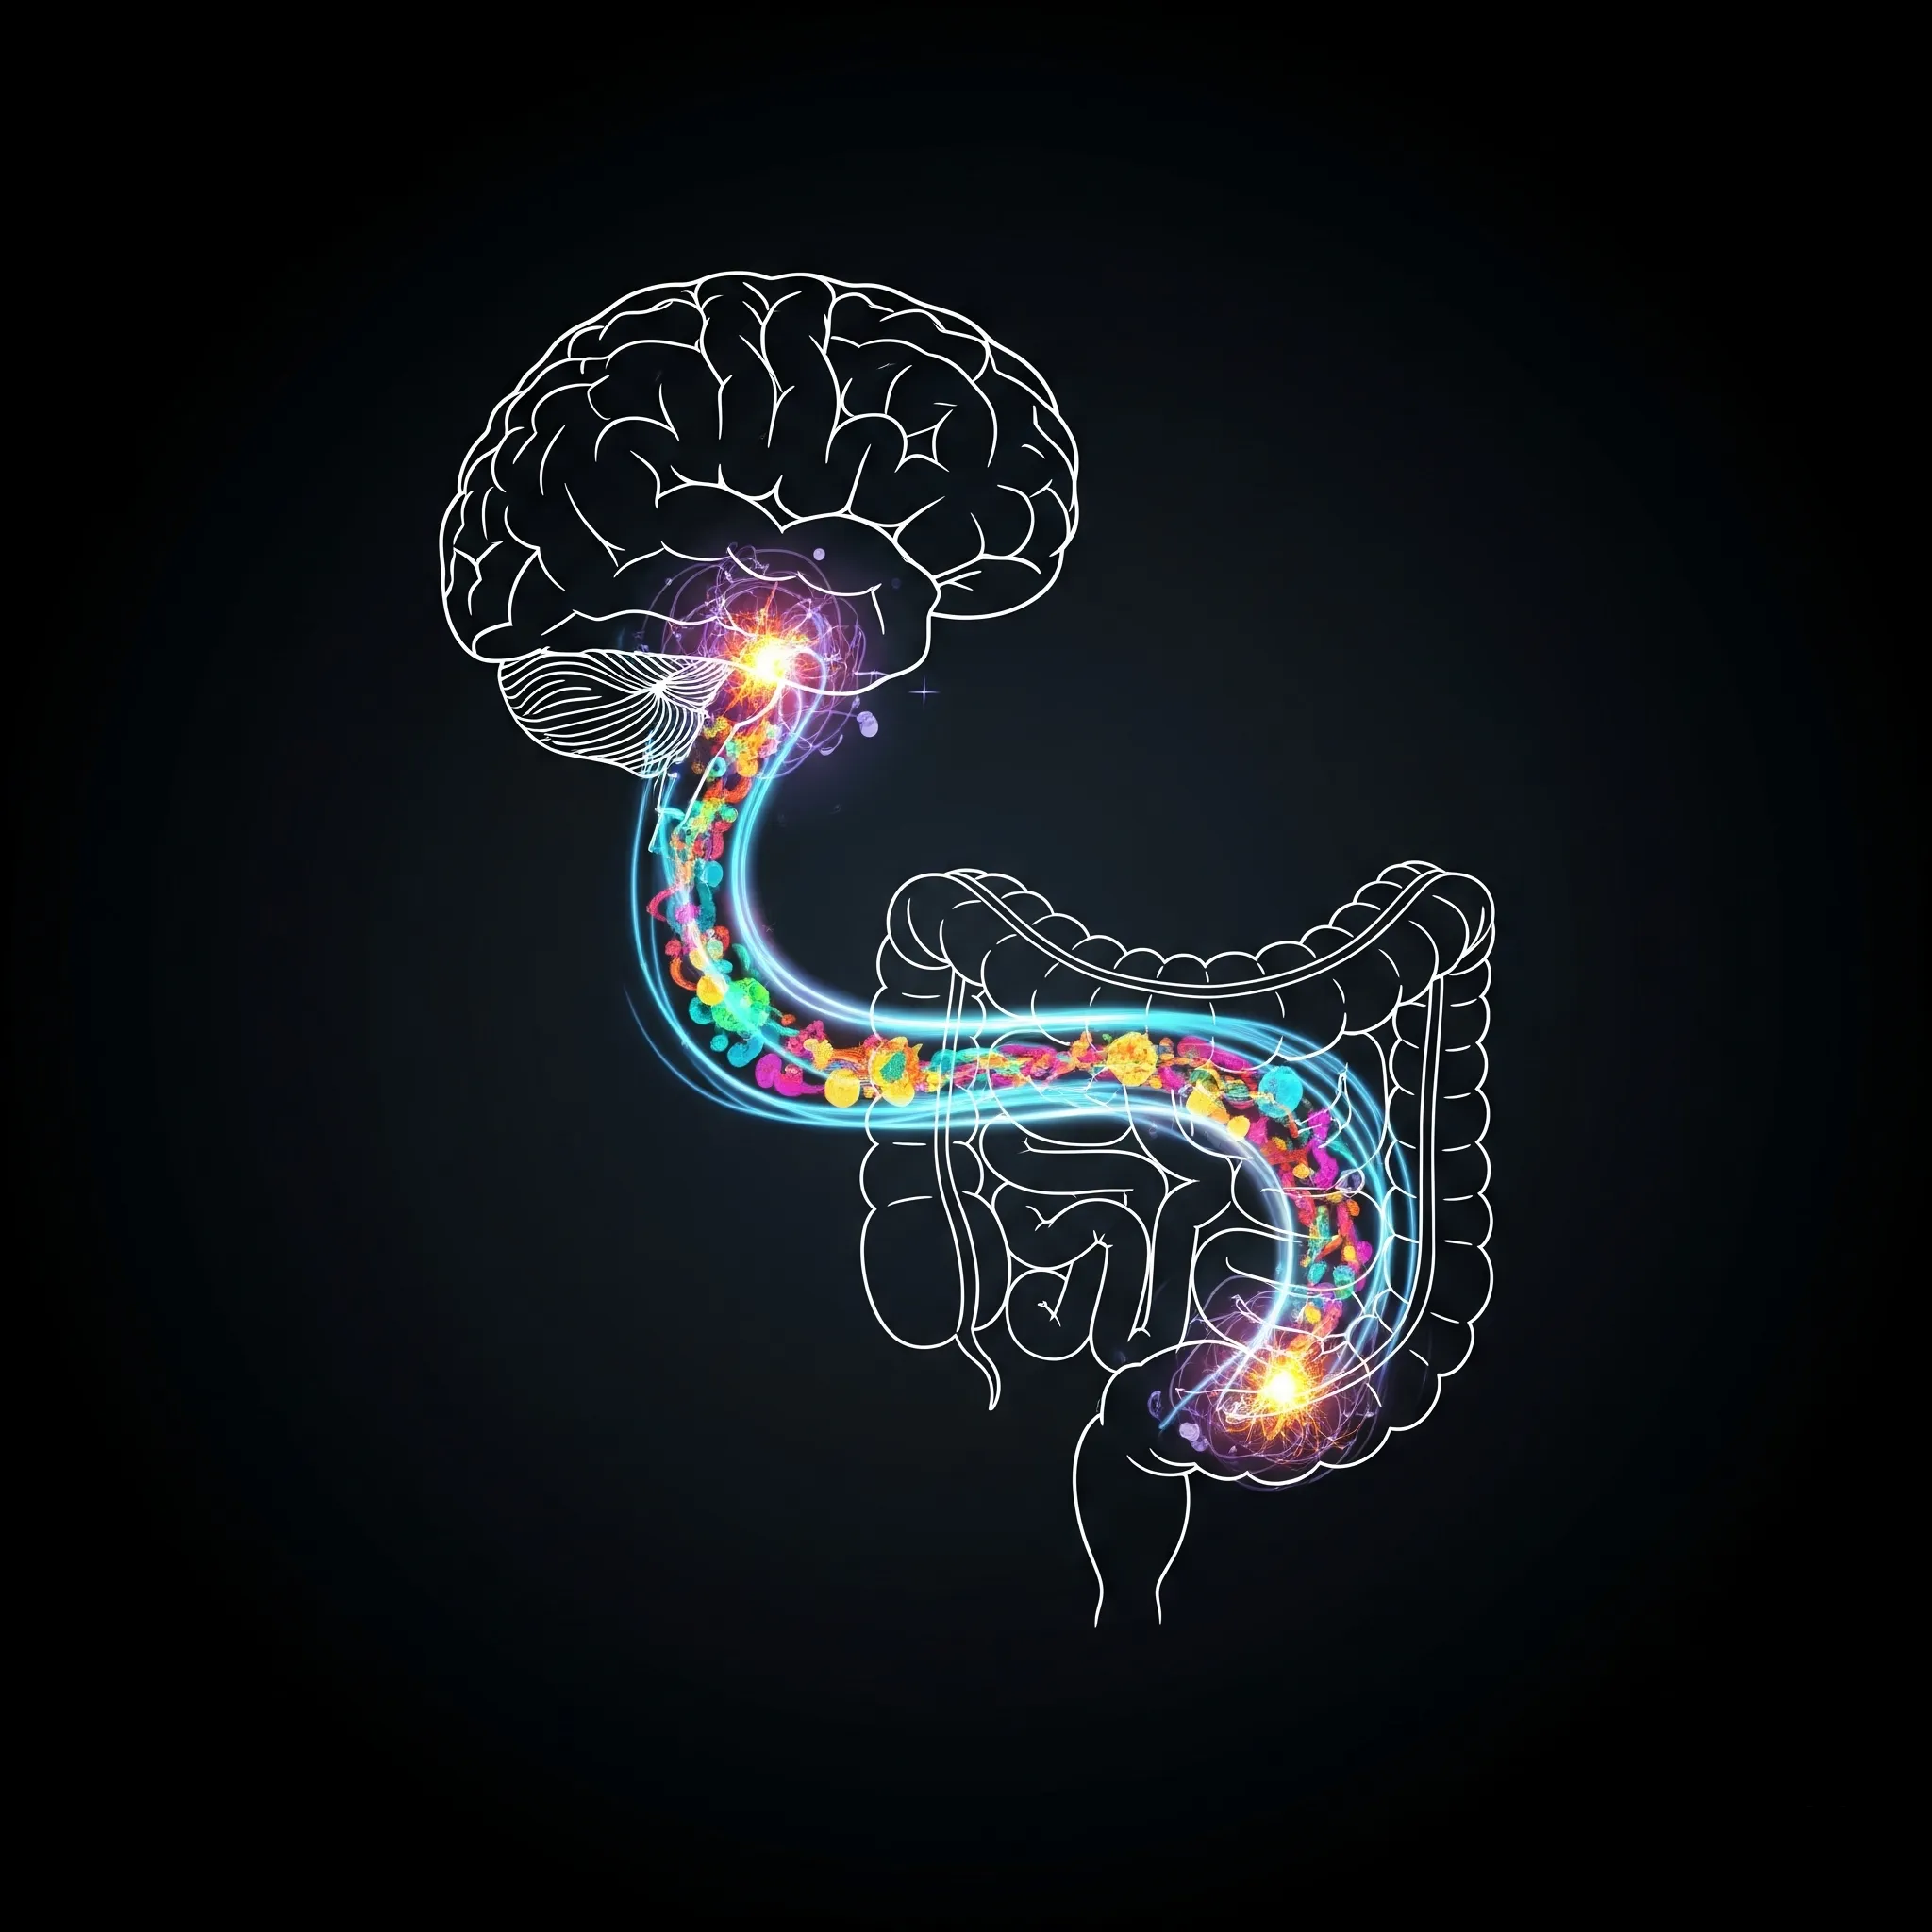

특별한 이유 없이 기분이 가라앉고, 무기력한 날이 계속되시나요? 우리는 보통 이런 감정의 문제를 '뇌'나 '마음'의 문제라고만 생각합니다. 하지만 만약, 그 모든 문제의 시작이 뜻밖에도 우리의 **'장(腸)'**에 있다면 어떨까요? 최근 과학계는 장을 **'제2의 뇌(The Second Brain)'**라고 부르며, 장 건강이 우리의 감정과 정신 상태에 미치는 막대한 영향력을 재조명하고 있습니다. 오늘은 어쩌면 당신의 우울감의 진짜 원인일지 모를 '장누수 증후군'과, 장을 살려 마음을 치유하는 방법에 대해 알아보겠습니다. 🌿

1. '장누수 증후군', 당신의 뇌를 공격한다 🧠

문제는, 혈관으로 침투한 염증 물질들이 뇌의 방어막인 혈뇌장벽(Blood-Brain Barrier)마저 약화시키고 뇌에 미세 염증을 유발한다는 것입니다. 뇌 염증은 기분과 감정을 조절하는 신경전달물질 시스템에 교란을 일으켜 우울감, 불안감, 집중력 저하, '브레인 포그(Brain Fog)' 와 같은 정신적 증상을 직접적으로 유발할 수 있습니다.